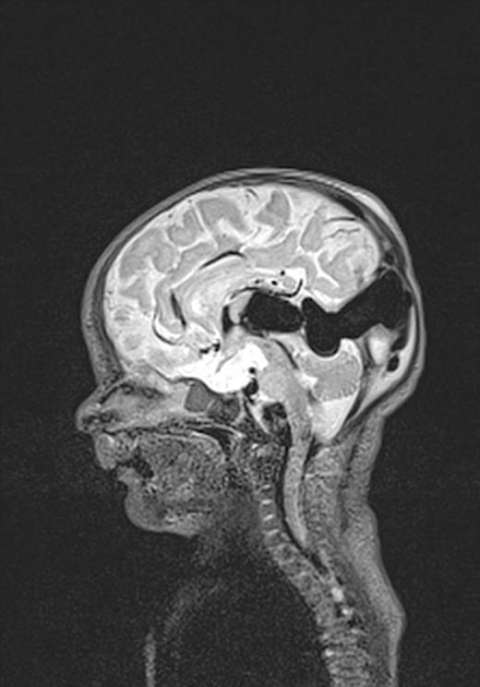

The vein of Galen malformation (also known as VGAM or VOGM) is a rare congenital blood vessel malformation in the brain that develops prenatally. A vein of Galen malformation is a tangled mass of abnormal connection of the arteries and the median prosencephalic vein of Markowski. However most people refer to this as the vein of Galen. This congenital malformation develops between weeks six and eleven in embryonic and fetal development. It is the most common arteriovenous malformation (a deformity that includes veins and arteries) in fetuses.

The capillaries in this tangled mass, which are supposed to slow down blood flow and allow for oxygen exchange into the surrounding tissues, are missing, so blood flows directly from the arteries to the veins without supplying the surrounding tissues with oxygen and nutrients. This supply of blood travels almost immediately to the heart, which may overwhelm the heart, leading to congestive heart failure. The vein of Galen defect is occasionally seen upon prenatal ultrasound examination, but generally it is not seen until birth.

- Cranial MRI and/or CT Scan (performed with or without contrast medium) - Cranial imaging can assist in confirming the diagnosis of VGAM and determine whether hydrocephalus is present, as well. Non invasive MR angiography can provide very useful information for treatment planning.